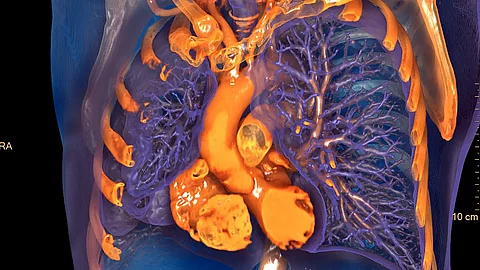

Zum Funktionsumfang von IntelliSpace Portal 12 gehört außerdem ein neues Tool für das fotorealistische Volume Rendering.7 Mit einer virtuellen, frei beweglichen Lichtquelle lassen sich bestimmte Bereiche gezielt illuminieren und die Plastizität der 3D-Strukturen verstärken.